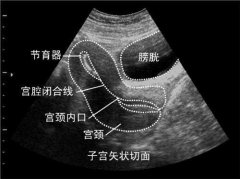

長在子宮頸上的“青春痘” 大為醫(yī)用B超為您淺析

現(xiàn)在很多朋友都有了自我保健的意識,主動體檢的人越來越多,宮頸納氏囊腫(簡稱納囊)也因此而更多的在超聲檢查中被發(fā)現(xiàn)。...